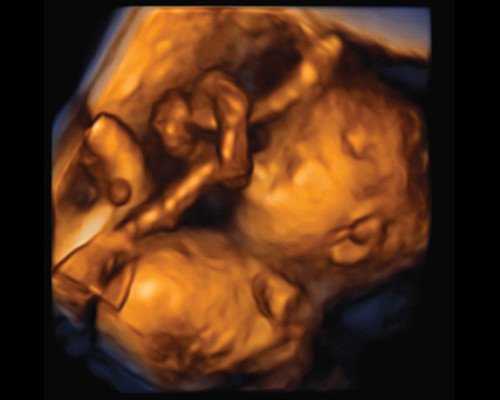

В настоящей статье представлено описание случая ИУП, диагностированного у плода с помощью двухмерной эхографии в 18 нед беременности при динамическом наблюдении в течение исследования, а затем идентифицированного с помощью других различных режимов, в том числе объемной реконструкции, а также подтвержденного после рождения ребенка при осмотре последа.

При исследовании в В-режиме экстраэмбриональных структур в амниотической полости на фоне нормального количества околоплодных вод среди множества тесно прилегающих друг к другу петель пуповины обнаружено несколько, не менявших характера своего первоначального расположения при изменении положения пациентки и движениях плода на протяжении всего исследования. После изучения данного участка в различных плоскостях с применением режимов допплеровской и недопплеровской визуализации кровотока был идентифицирован ИУП, прежде всего по характерной картине его поперечного среза (рис. 1). C помощью объемной эхографии предварительный пренатальный диагноз "ИУП" был окончательно уточнен (рис. 2).

Рис. 1. Характерная эхографическая картина истинного узла пуповины.